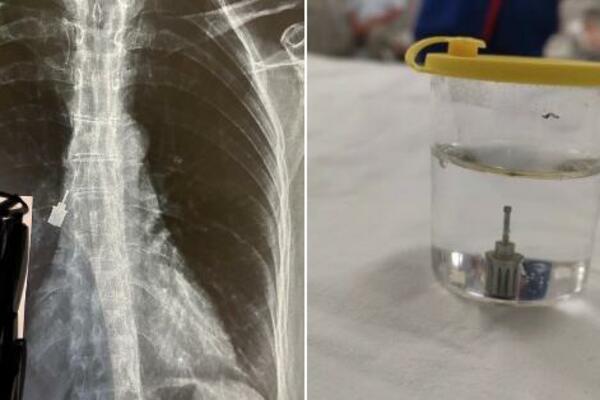

SRBIN UMALO IZGUBIO ŽIVOT ZBOG JEDNOG ŠRAFA: Putovanje na more moglo SKUPO DA GA KOŠTA, ovo može SVAKOM DA SE DESI